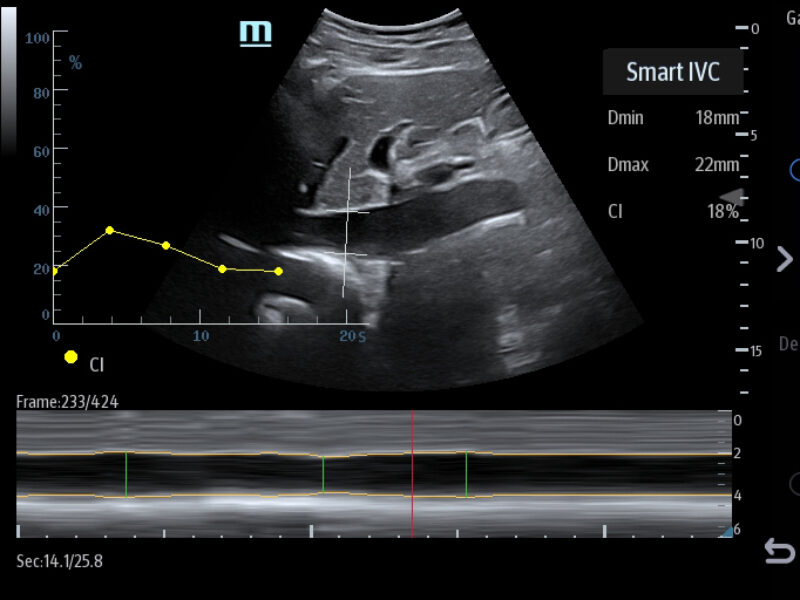

Images